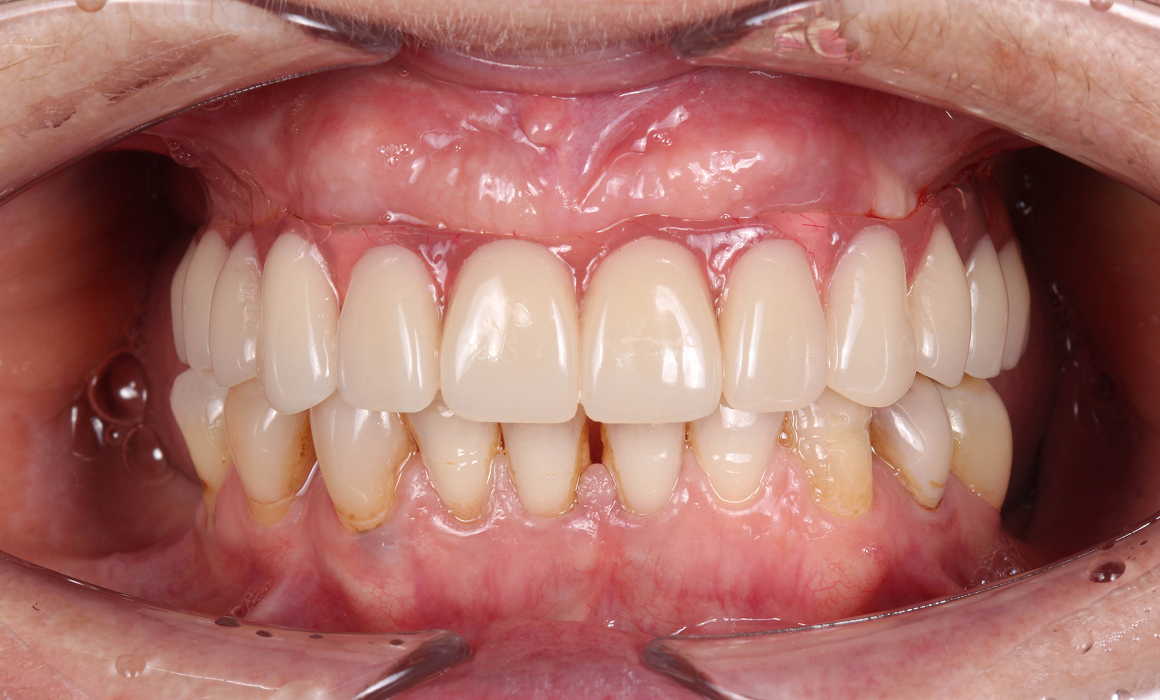

Улыбка до/после

Несъемные протезы

Постоянное протезирование после приживления имплантов

Циркониевый протез

• Высокая эстетика

• Срок службы 10-15 лет

• Хорошая прочность

Стоимость 400 000 ₽